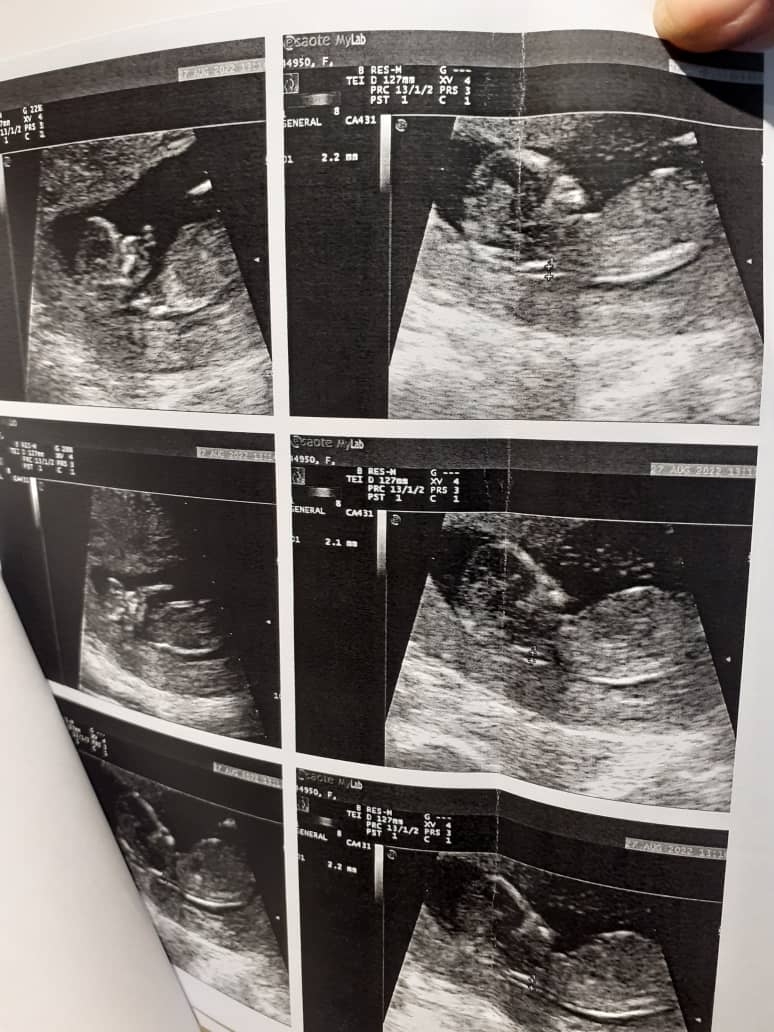

سلام به روی ماهتون عزیزم در سونوگرافی انجام شده تمام موارد بررسی شده از جمله وضعیتجنین، حجم مایع آمنیوتیک، طول سرویکس ، جایگاه جفت، ضربان قلب و همچنین میزان ان تی (NT) در محدوده نرمال قرار دارد و از این بابت جای نگرانی نیست اما بخش آزمایش خون غربالگری را فراموش نکنید تا بتوان تفسیر صحیحی داشت🌹